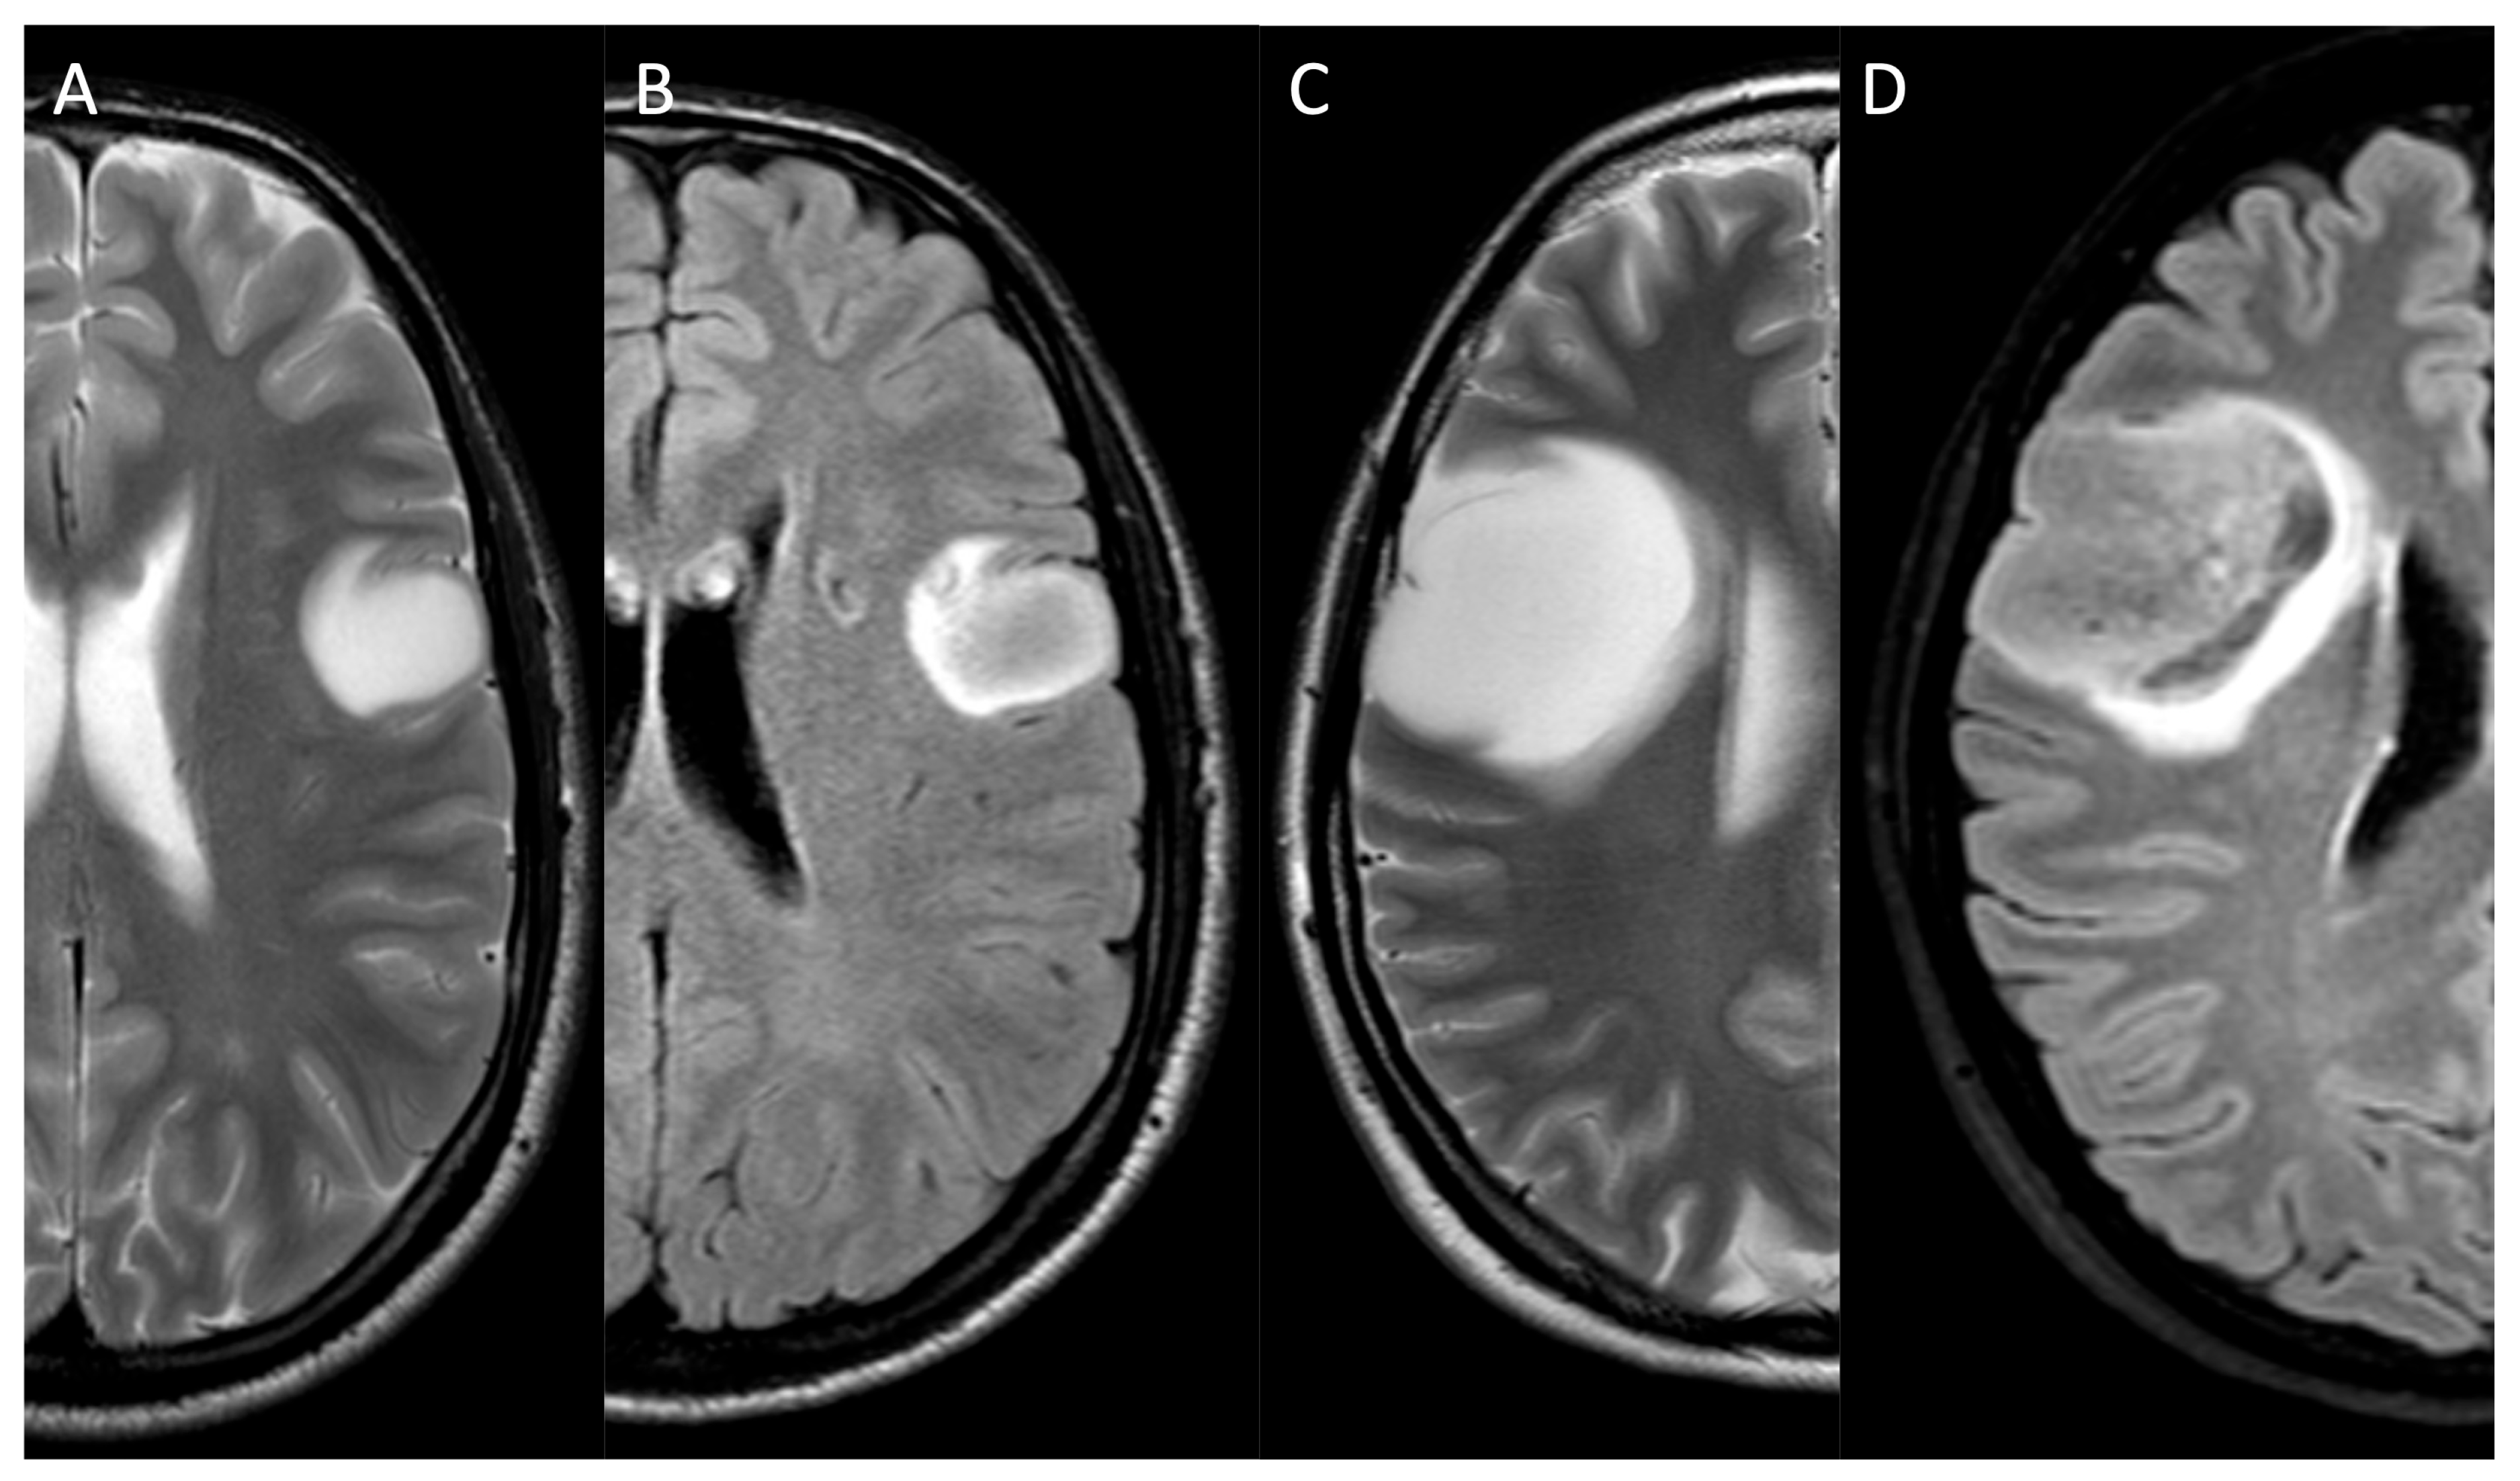

- Patel, S.H.; Poisson, L.M.; Brat, D.J.; Zhou, Y.; Cooper, L.; Snuderl, M.; Thomas, C.; Franceschi, A.M.; Griffith, B.; Flanders, A.E.; et al. T2-FLAIR Mismatch, an Imaging Biomarker for IDH and 1p/19q Status in Lower-Grade Gliomas: A TCGA/TCIA Project. Clin. Cancer Res. 2017, 23, 6078–6085. [Google Scholar]

- Li, M.; Wang, J.; Chen, X.; Dong, G.; Zhang, W.; Shen, S.; Jiang, H.; Yang, C.; Zhang, X.; Zhao, X.; et al. The Sinuous, Wave-like Intratumoral-Wall Sign Is a Sensitive and Specific Radiological Biomarker for Oligodendrogliomas. Eur. Radiol. 2023, 33, 4440–4452. [Google Scholar] [CrossRef]